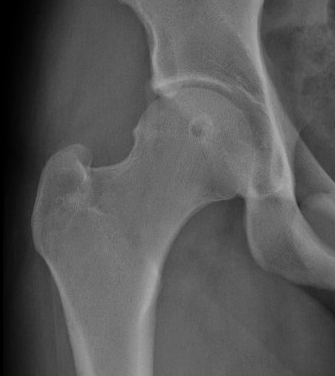

Labral tear

Cam / pincer impingement

Acetabular rim trim / Acetabuloplasty

Pincer resection

CAM resection